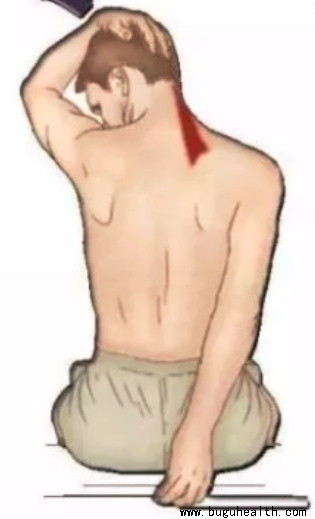

- 布骨医学科普:天气寒冷,这块肌肉容易僵硬劳损! BuGuRMC布骨康复医疗中心 ,2023-11-26

- 这块肌肉就是头夹肌,头夹肌是位于颈部后方的肌肉。夏天经常的吹空调,冬天受到寒冷的刺激,再加上经常维持特定头部姿势,就很容易导致这块肌肉僵硬及劳损。保持温暖、正确的姿势、适当伸展、按摩和热敷等物理疗法都可以很好地缓解肌肉的紧张和减轻不适感。.....